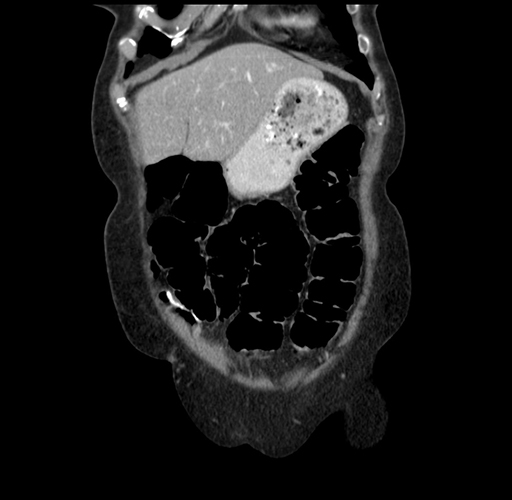

Pre-Chemo: Axial Venous

Axial Venous